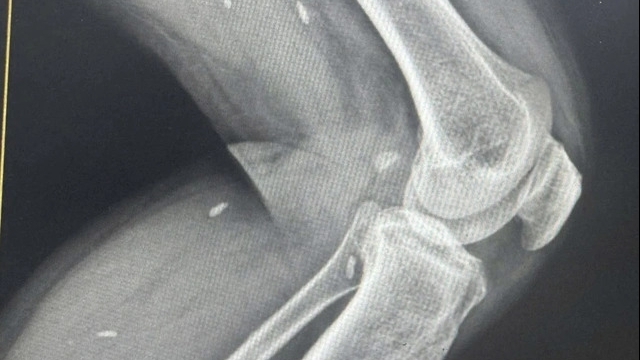

Lúc này bệnh nhi được xác định là đa chấn thương: Chấn thương sọ não, chấn thương ngực, tràn máu màng phổi, chảy máu trong ổ bụng do vỡ gan, vỡ tụy trung tâm, vỡ cơ hoành làm các tạng trong bụng lên ngực, vỡ xương chậu, gãy xương đùi.